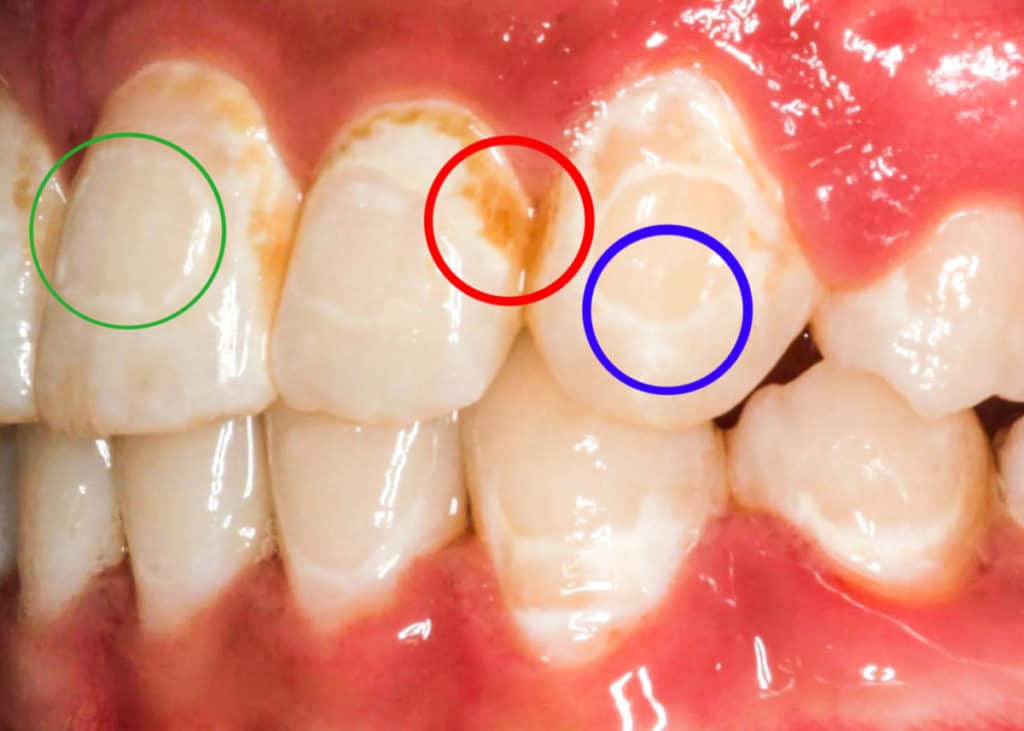

Braces Glue Spots . Some of these options include dental bleaching, microabrasion, enamel infiltration, cosmetic bonding, and dental veneers. braces stains typically take the form of white spots on the teeth after your braces come off. try baking soda — you can create a paste with baking soda and water and gently brush your teeth and braces. braces are an effective orthodontic treatment for straightening misaligned teeth. These white spots are areas of decalcification, or very. 10 ways to prevent stains and white spots on teeth after braces. Failing to properly clean teeth while wearing braces can cause. A cosmetic dentist can help you with different treatment options for white spot removal after braces. Braces can leave stains, but it’s important to use the right treatments to restore your smile. white spots on teeth after braces cannot be removed with a regular oral care routine. orthodontists recommend performing professional tooth cleaning or scaling after braces because it’s common to have tartar, plaque, and stains after braces. This will also remove glues that are used for braces attached to teeth.

braces are an effective orthodontic treatment for straightening misaligned teeth. These white spots are areas of decalcification, or very. orthodontists recommend performing professional tooth cleaning or scaling after braces because it’s common to have tartar, plaque, and stains after braces. 10 ways to prevent stains and white spots on teeth after braces. try baking soda — you can create a paste with baking soda and water and gently brush your teeth and braces. braces stains typically take the form of white spots on the teeth after your braces come off. Some of these options include dental bleaching, microabrasion, enamel infiltration, cosmetic bonding, and dental veneers. Failing to properly clean teeth while wearing braces can cause. Braces can leave stains, but it’s important to use the right treatments to restore your smile. white spots on teeth after braces cannot be removed with a regular oral care routine.